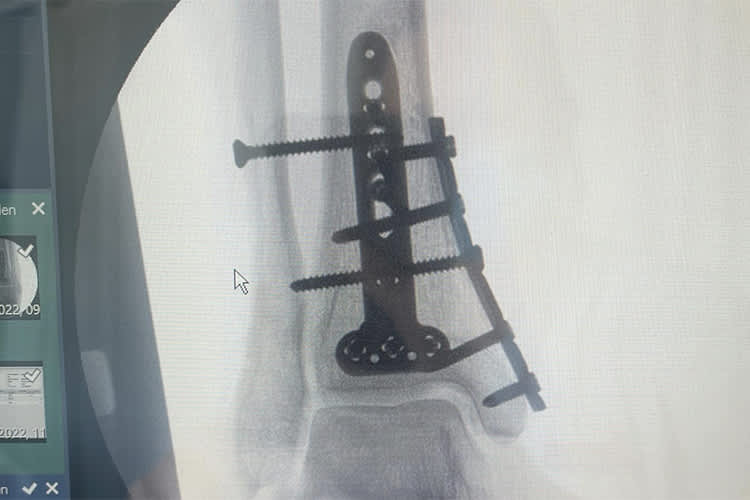

Wenige Tage bevor BMW im März mit den Testfahrten für die Superbike-WM 2022 begann, hat sich Michael van der Mark beim Mountainbike-Training oberhalb des Sprunggelenks mehrfach den rechten Unterschenkel gebrochen. Der Niederländer verpasste daraufhin insgesamt sechs Testtage in Misano, Barcelona und Aragon, auch beim Saisonstart in Spanien fehlte er.